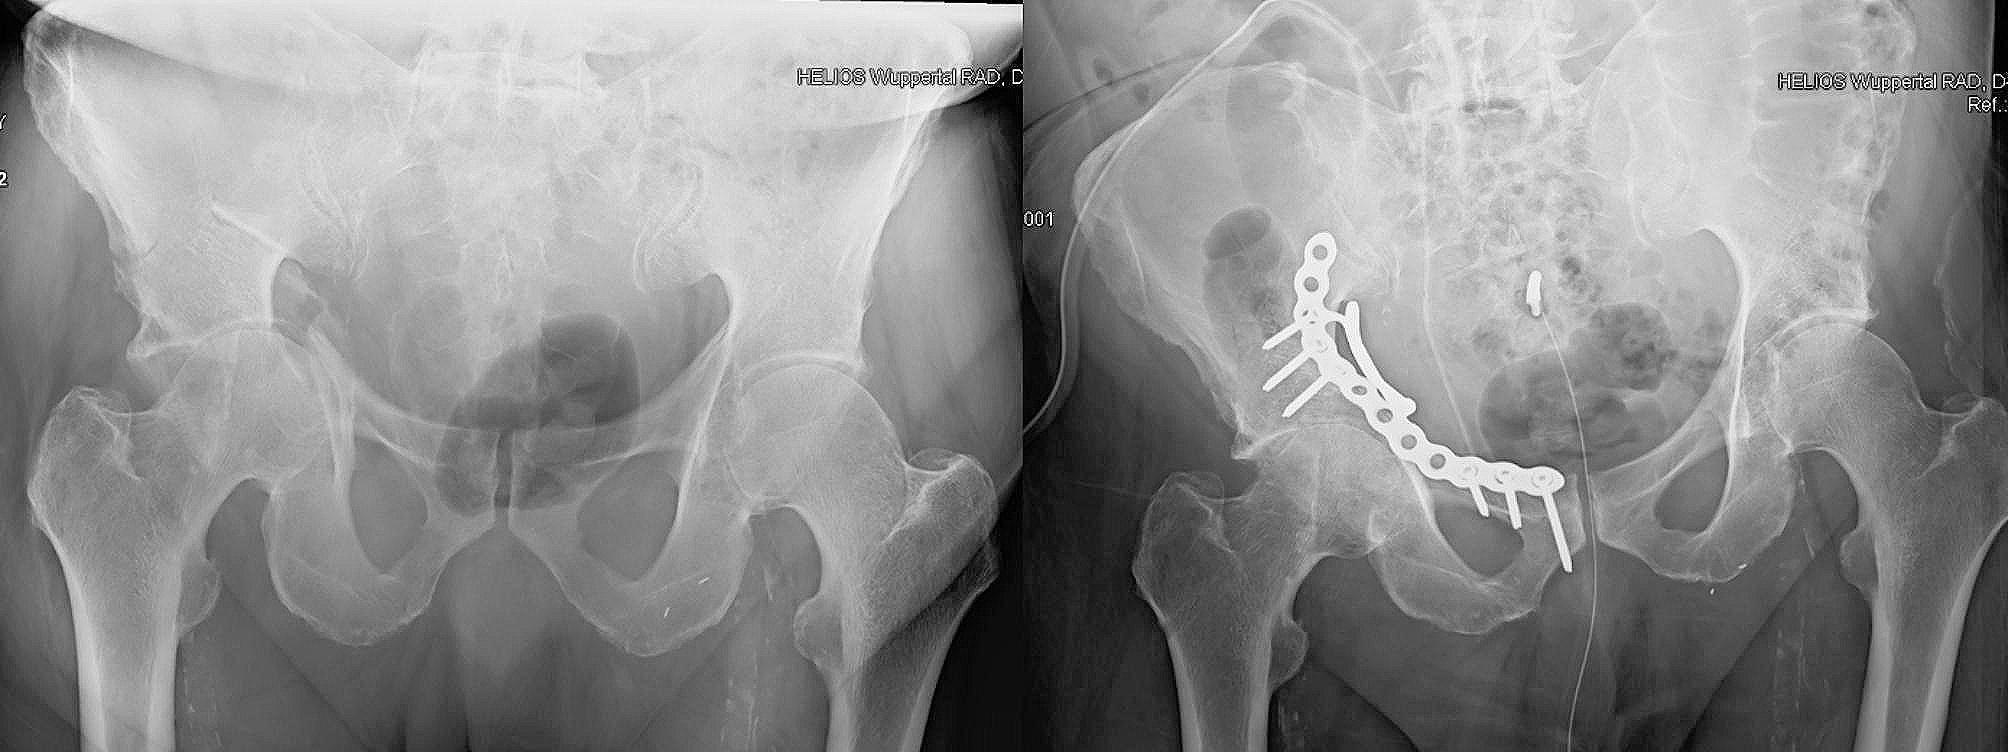

机器人辅助髋臼前柱钢板固定术——一种新技术的临床描述

Robotic-assisted plate fixation of the anterior acetabulum - clinical description of a new technique.

We present a detailed procedure for the robotic-assisted plate osteosynthesis of an anterior acetabular fracture. The purpose of this work was to describe a robotic-assisted minimally invasive technique as a possible method for reducing complications, pain, and hospitalization. Another goal was to present technical recommendations and to assess potential pitfalls and problems of the new surgical approach.

METHODS

Surgery was performed in an interdisciplinary setting by an experienced orthopedic surgeon and a urologist. The DaVinci System with standard instruments was used. Reduction was achieved through indirect traction of a pin that was introduced into the femoral neck and direct manipulation via the plate. The plate position and fixation were achieved through 7 additional minimally invasive incisions.

RESULTS

The technique has multiple advantages, such as no detachment of the rectus abdominal muscle, a small skin incision, and minimal blood loss. Furthermore, this approach might lower the incidence of hernia formation, infection, and postoperative pain.

我们介绍一种用于髋臼前柱骨折机器人辅助钢板内固定的详细手术步骤。这项工作的目的是描述一种机器人辅助的微创技术,作为减少并发症、疼痛和住院时间的一种可能方法。另一个目标是提出技术建议,并评估这种新手术方法的潜在陷阱和问题。

手术在多学科环境下由一位经验丰富的骨科医生和一位泌尿科医生进行。使用配备标准器械的达芬奇系统。通过将一根针插入股骨颈进行间接牵引,并通过钢板进行直接操作来实现复位。通过另外7个微创切口来实现钢板的定位和固定。

结果